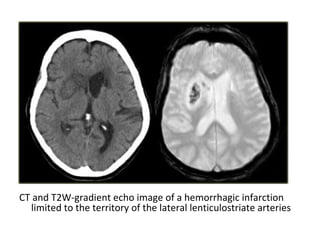

CT and T2W-gradient echo image of a hemorrhagic infarction

limited to the territory of the lateral lenticulostriate arteries